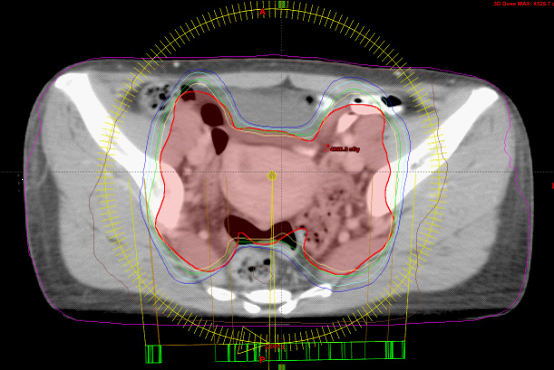

作为目前国际上最先进的放射治疗技术,VMAT具有"快、准、优"的特点。在时间方面,传统放射治疗过程需15-30分钟,而该技术将整个治疗过程缩短至2-6分钟,有效提高肿瘤控制率;在准确程度上,该技术可在360度多弧任何角度范围内旋转照射,比传统治疗方式照射范围更大。同时,该技术还能调整控制放射线在肿瘤上的强度,每次治疗时可立即取得三维电脑断层扫瞄影像并做精准治疗定位;此外,VMAT治疗技术不仅让放射线随着肿瘤厚度调节强度,还能根据肿瘤体积各部位的厚薄不同,给予最适合的放射线强度,同时避开在肿瘤中间或凹陷处的如眼球、脊髓等重要危及器官,增加肿瘤控制率,降低正常组织并发症,减少副作用。

VMAT治疗技术在放射治疗前、放射治疗中能实时对肿瘤及肿瘤周围正常器官进行CT扫描监控,根据肿瘤及器官位置的变化、肿瘤的厚度、体积等调整治疗条件,使放射线紧紧跟踪肿瘤进行精准治疗。此外,该项技术还能随时对肿瘤放射剂量的精度进行调整,克服呼吸运动、器官蠕动及日常摆位误差,人体重要器官和组织能得到更好的保护。